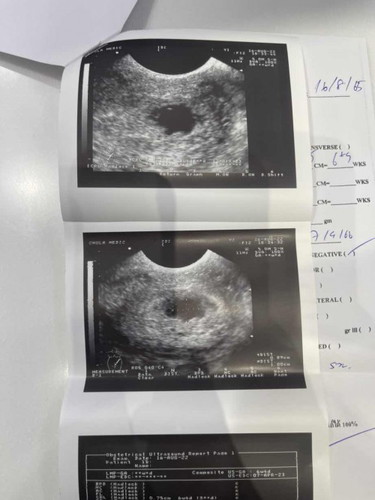

หมอบอกว่าเจอเด็กแต่ไม่เจอหัวใจ ถุงตั้งครรภ์ไม่สวยเครียดมากเลยคะมีใครเคยเป็นบ้างคะ

ในใบอัลตร้าซาวขึ้น6วีค5วันค่ะ

Thành viên VIP